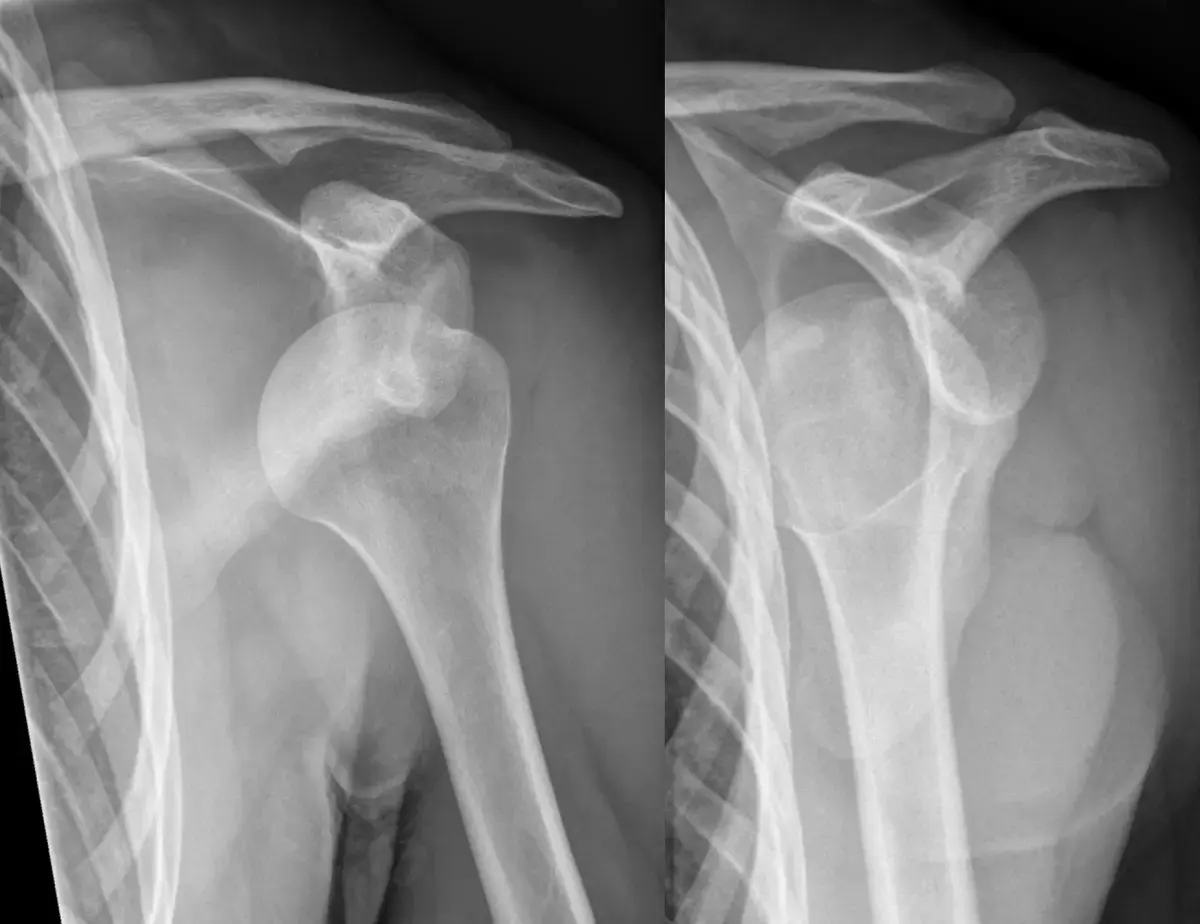

* الأشعة السينية (X-rays): هي الفحص الأولي الأكثر شيوعًا، وتستخدم لتقييم العظام، الكشف عن الكسور، التشوهات العظمية، وتغيرات التهاب المفاصل.